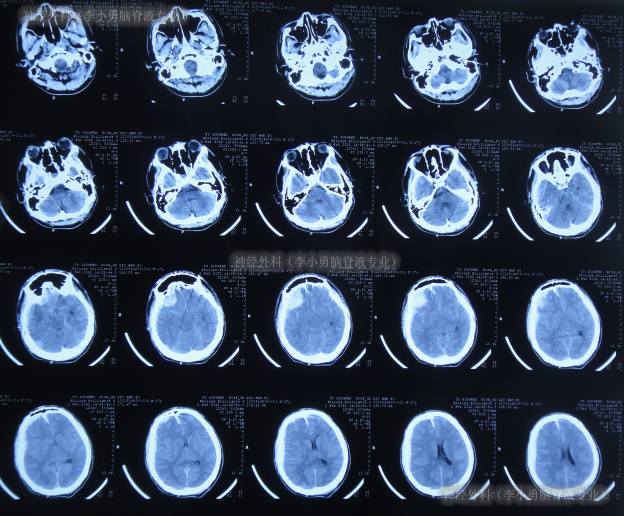

患者于2022年2月2日,不慎摔倒头部磕到地面,当时呈嗜睡状态,呕吐1次,大小便失禁,由120急送至当地县某医院,查头颅CT示右额部血肿(片子丢失),当即转至上级的河北省唐山市某医院,查头颅CT示右额部血肿、脑疝(图-1);检查期间出现昏迷、呕吐、四肢强直。

图-1:2022年2月2日头颅CT

急诊当天进行了去骨瓣减压+血肿清除术(图-2)。

图-2:2022年2月2日术后头颅CT

去骨瓣减压+血肿清除术后第2天即2022年2月3日,头颅CT示出血有增多(图-3)。

图-3:2022年2月3日头颅CT

术后3天即2022年2月4日,患者苏醒,能言语,但遗留左侧肢体不能活动,低钠血症,查头颅CT示仍有较多积血(图-4)。

图-4:2022年2月4日头颅CT